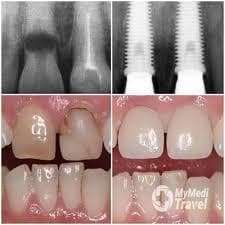

Bone Augmentation at Same Day Dental Implants

Same Day Dental Implants, can be found in Dubai Health Care City, Dubai, United Arab Emirates and offers its patients Bone Augmentation procedures as well as 55 other procedures, across 2 different procedure categories

. At present, there is no pricing information for Bone Augmentation procedures at Same Day Dental Implants. The pricing information is quite specialised, so it's only available on request.